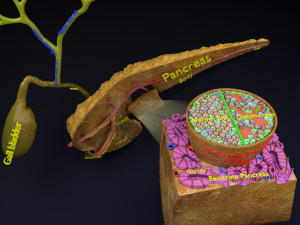

A blend model of brain along with its covering layers (meninges), skull bone and scalp labelled in detail and anatomically precise. The parts depicted are white, gray, pia, arachnoid, dura, bone, skin, fat, aponeurosis, periosteum, falx cerebri and more.